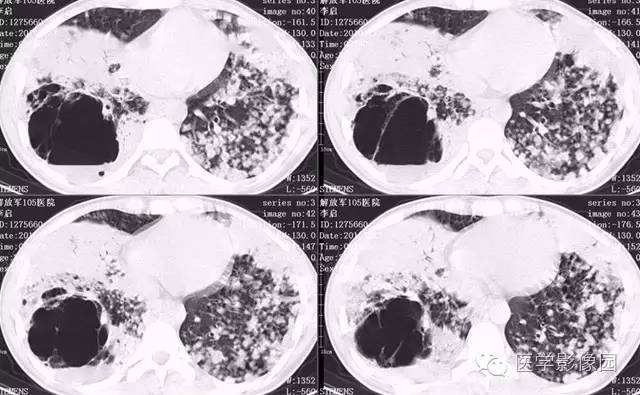

弥漫性肺泡细胞癌1例CT影像表现

病理结果:弥漫性肺泡细胞癌

弥漫性肺泡癌的主要临床及CT表现:临床表现无明显特征, 随着病情的进展, 咳嗽、 咳白痰、 进行性气促。CT表现 为病变分布有两种情况:病变累及一个肺段或肺叶;病变广泛分布于两肺。可归纳为5个特征性征象:蜂房征;支气管充气征;磨玻璃征;血管造影征;两肺弥漫分布的斑片状与结节影。